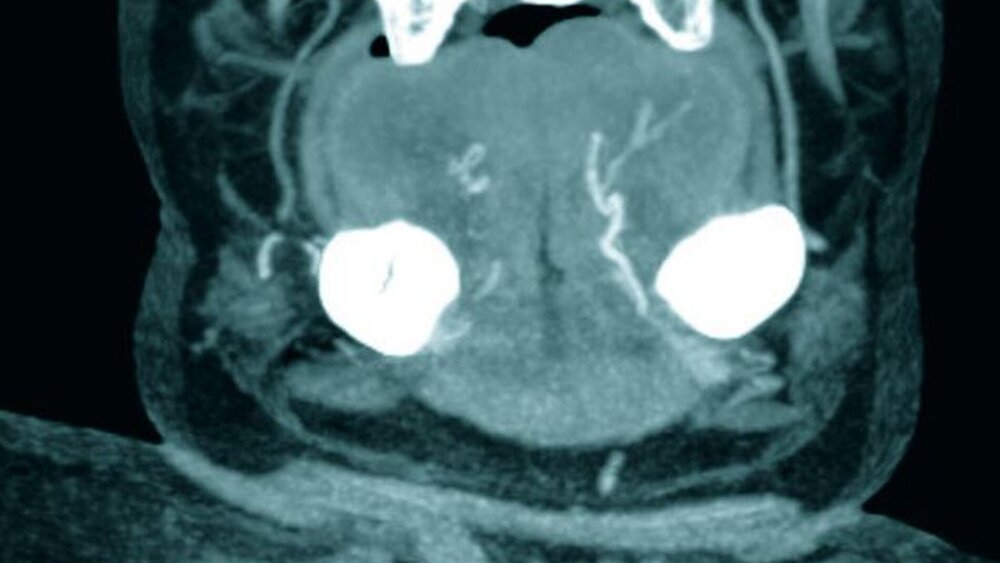

Zur Therapie der Zungenschwellung wurden 500 mg Solu-Decortin intravenös verabreicht und ein Routinelabor abgenommen. Eine Schutzintubation wurde zunächst nicht vorgenommen, da die Schwellung sistierte. Anschließend wurde zur weiteren Abklärung der Zungenschwellung und neurologischen Auffälligkeiten eine Craniale Computertomographie (CCT) des Kopfes durchgeführt. Hierbei zeigte sich eine hämorrhagisch durchsetzte Zunge mit begleitender ödematöser Schwellung ohne Anzeichen für eine umschriebene Einblutung oder für eine assoziierte Gefäßmalformation in der Zunge (Abbildung 2). Das CCT bot einen postischämischen Hirnbefund. Im durchgeführten Routinelabor fiel ein deutlich erniedrigter Quick-Wert 10 Prozent bei sonst normalen Parametern auf. Nach Rücksprache mit dem Hausarzt ließ sich eruieren, dass die Patientin vor einem Monat einen ischämischen Schlaganfall und eine tiefe Beinvenenthrombose erlitten hatte. In der Folge wurde die Patientin mit Phenprocoumon eingestellt, hatte jedoch täglich eine Routinedosis eingenommen, da sie zu einer täglichen Anpassung aufgrund des neurologischen Defizits nicht in der Lage war. Nach zweitägiger Überwachung der Patientin auf der Intensivstation und sukzessiver Befundbesserung sowie Normalisierung der Gerinnungsparameter konnte die Patientin auf Normalstation verlegt werden.